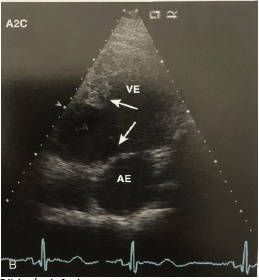

Paciente do sexo masculino de 75 anos, iniciou há cinco anos quadro de episódios recorrentes de dispneia aos esforços e edema de membros inferiores necessitando frequentemente buscar atendimento médico de urgência, não é portador de doença hipertensiva nem de outras comorbidades. Na última visita ao setor de urgência, apresentou-se com quadro clínico de insuficiência cardíaca biventricular e edema de extremidades. À investigação com exames complementares foi realizado ECG que evidenciou complexos QRS de baixa voltagem.

Assinale a alternativa correta que contém o provável diagnóstico, de acordo com os dados acima e a imagem ecocardiográfica abaixo.